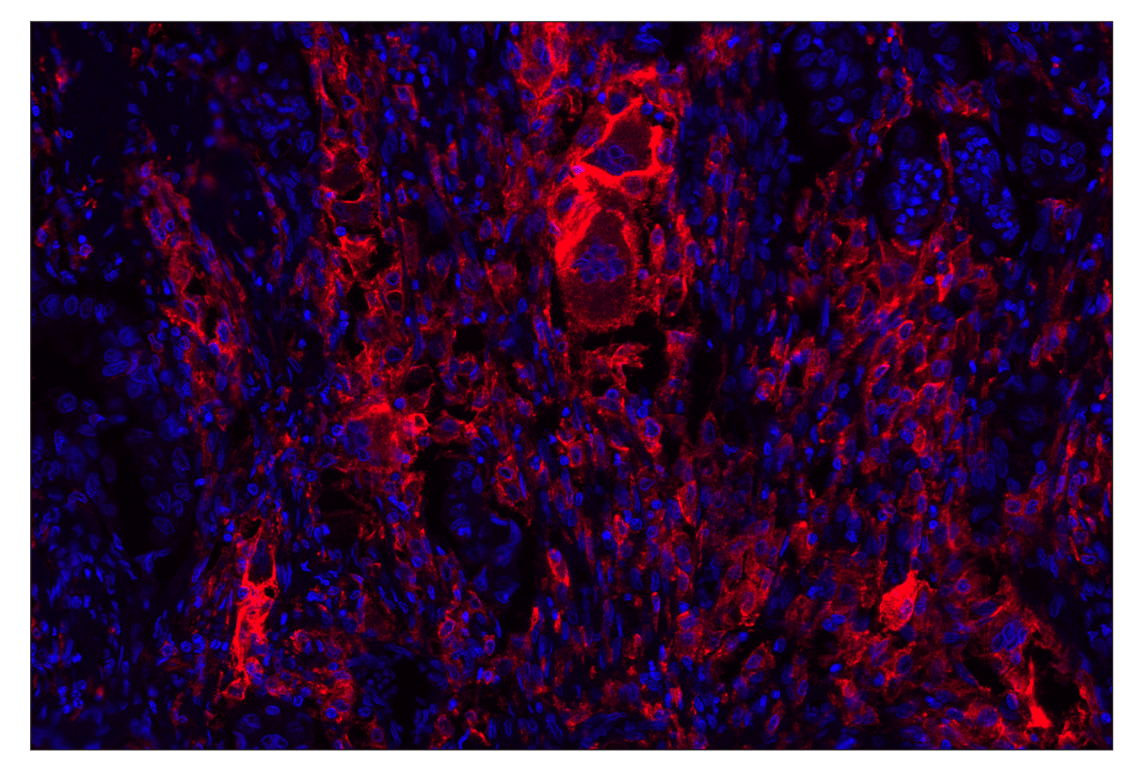

Immunohistochemistry (Paraffin) 1:50 - 1:200

CD206/MRC1 (E2L9N) Rabbit Monoclonal Antibody (Alexa Fluor® 647 Conjugate) recognizes endogenous levels of total CD206/MRC1 protein.